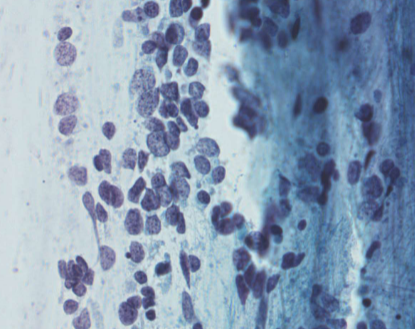

small cell carcinoma (SCLC)